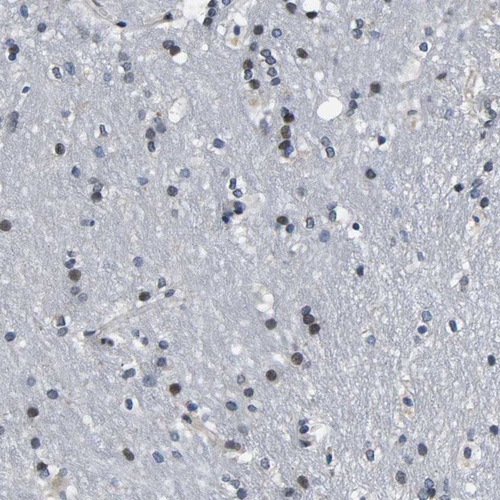

Immunohistochemical staining of human caudate shows moderate nuclear positivity in glial cells.